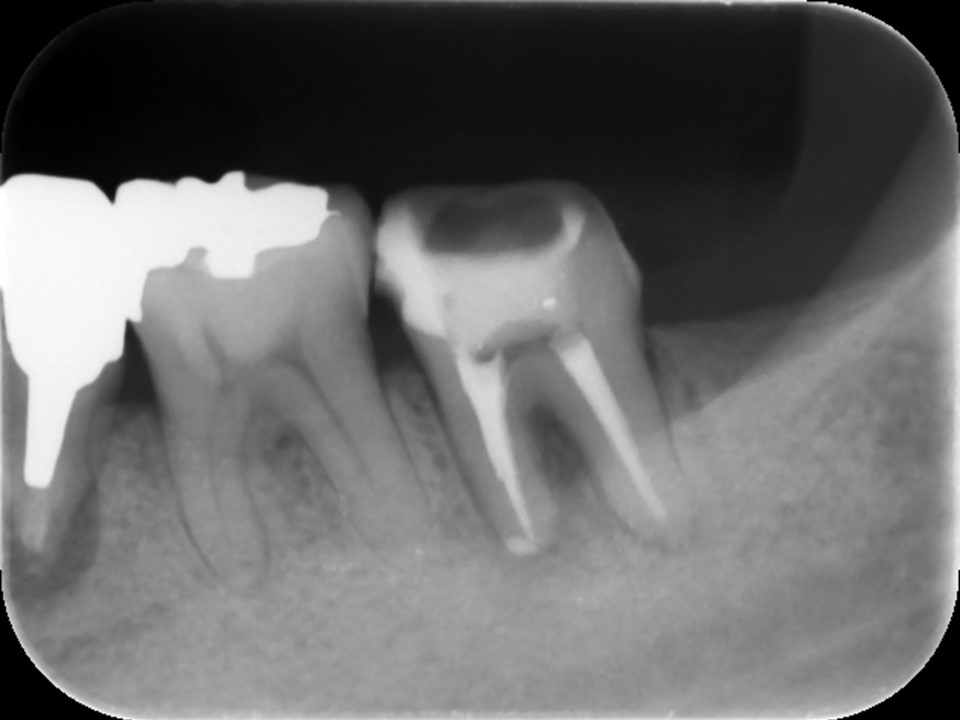

当該歯のレントゲンおよびCTによる診査にて、根尖部に根尖病巣と思われるX線透過像を認めました。また、歯根の側方には歯の方向を間違えて削った跡があり、パーフォレーション(穿孔、穴)が疑われました(下写真)。

治療前レントゲン | 治療前CT |

![]() |

術前のレントゲンおよびCT画像です。根尖部に根尖病変と思われるX線透過像を認めます(黄矢印)。歯根の側方には、方向を間違えて削ったと思われる跡が見られます。